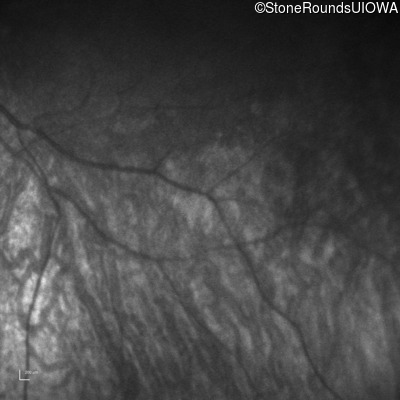

Infrared Fundus Photograph - Left -

No Light Perception

Exemplar

Expanded OCT Stack

×